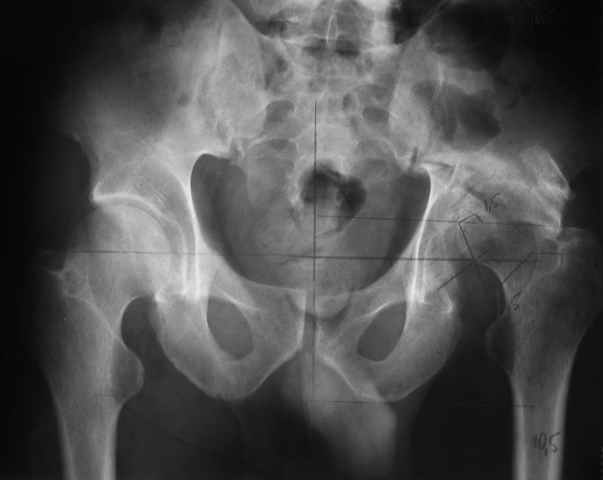

Dear All, The patient came to us for opinion regarding this # of pelvis which he sustained 5 months back.

He gives history of being on skin traction for 3,5months. After that he was advised partial weight bearing to be graduated to full weight bearing. Now the patient has difficulty in weight bearing as it is painful. He can walk a few steps only with the help of a walker. Hip movements are restricted and painful. Fl-90* ER-10* IR-0, shortening-4cm. He also had # of humerus and radius/ulna, which were plated and have united. The serial x-rays of the pelvis/Hip during these 5 months show that the hip joint has been in the same position. I have the CT pictures also but not digitalized as yet.

He is 47 years old, Class-1 officer.What are the options? Expert comments please.1. # Pelvis stabilization - Is it possible at 6 mths? And subsequently THR.

2. THR in this position- Cup positioning in a deformed pelvis?

It is a displaced and ununited fracture of the acetabulum, probably type C (AO). The pelvis is not fractured from what one can see of the sacro iliac joint.